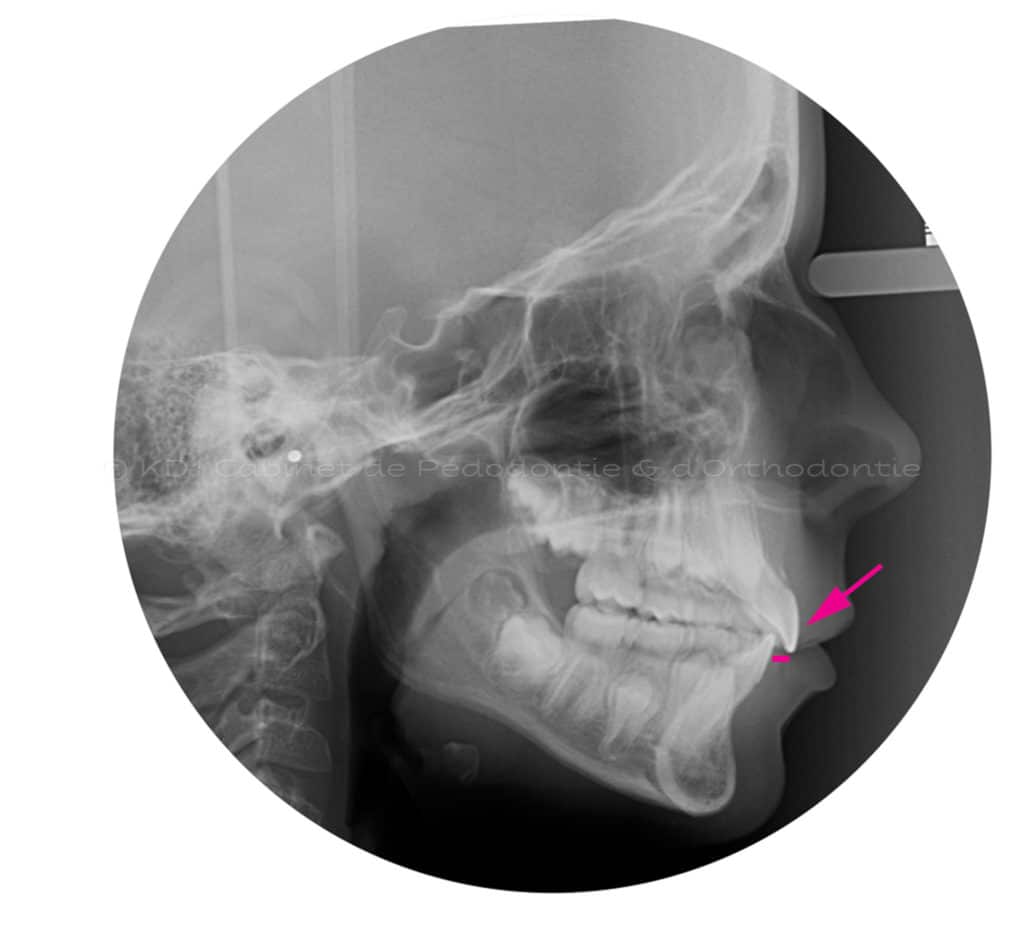

Cas #3 – Traitement avec un casque de traction maxillaire en dentition mixte (âge 9.5). Le but est de redresser les dents de devant (très penchées en avant) afin d’éviter les cassures de ces dents. Le recul de la dentition supérieure est possible avec ce dispositif extraoral. Un effet favorable indirect sur la mâchoire inférieure est à visible.